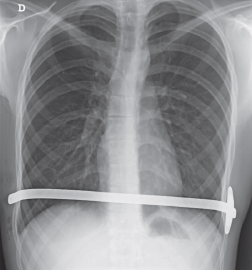

Pectus excavatum, manejo mínimamente invasivo con técnica de Nuss. Experiencia Instituto Nacional del Tórax.

Resultados: Se incluyeron 86 pacientes operados con técnica mínimamente invasiva en el período descrito. De ellos, 74 pacientes de sexo masculino. El promedio de edad al momento de la cirugía fue de 17,8 años. El principal motivo de consulta fue por desmedro estético que correspondió al 41,8% de los pacientes. Salvo en 1 paciente, en todo el resto se ocupó una sola barra. En nuestra serie hubo 12 pacientes que presentaron alguna complicación operatoria y 1 paciente fallecido. Hasta el cierre del seguimiento se retiraron 61 barras, 2 de ellas previo al período estipulado de tratamiento, por morbilidad. Hay 20 barras in situ y 4 pacientes de los cuales no se tiene registro por abandono de controles.

Discusión: El pectus excavatum es la más frecuente de las deformidades de la pared torácica, es 4 a 6 veces más frecuente en hombres que en mujeres. En general los pacientes son asintomáticos, aunque algunos pueden presentar síntomas cardiopulmonares. La reparación con cirugía mínimamente invasiva con técnica de Nuss aparece hoy en día como el gold standard de manejo.